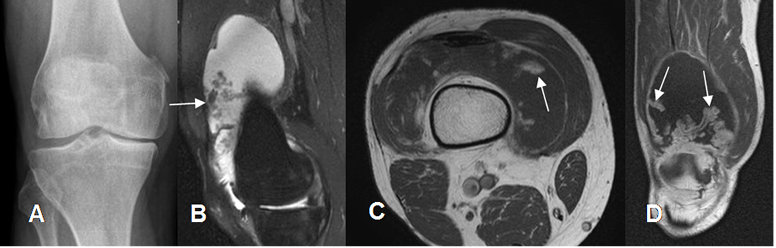

Fig 163 B. Lipoma arborescente.

A: Rx AP. No se encuentran alteraciones.

B: RM sagital en STIR. Abundante derrame articular, con proliferación sinovial hipointensa.

C: RM axial en T1 y D: RM coronal en T1 con contraste. La proliferación sinovial sigue la señal de la grasa subcutánea y realza con el contraste, por lipoma arborescente.